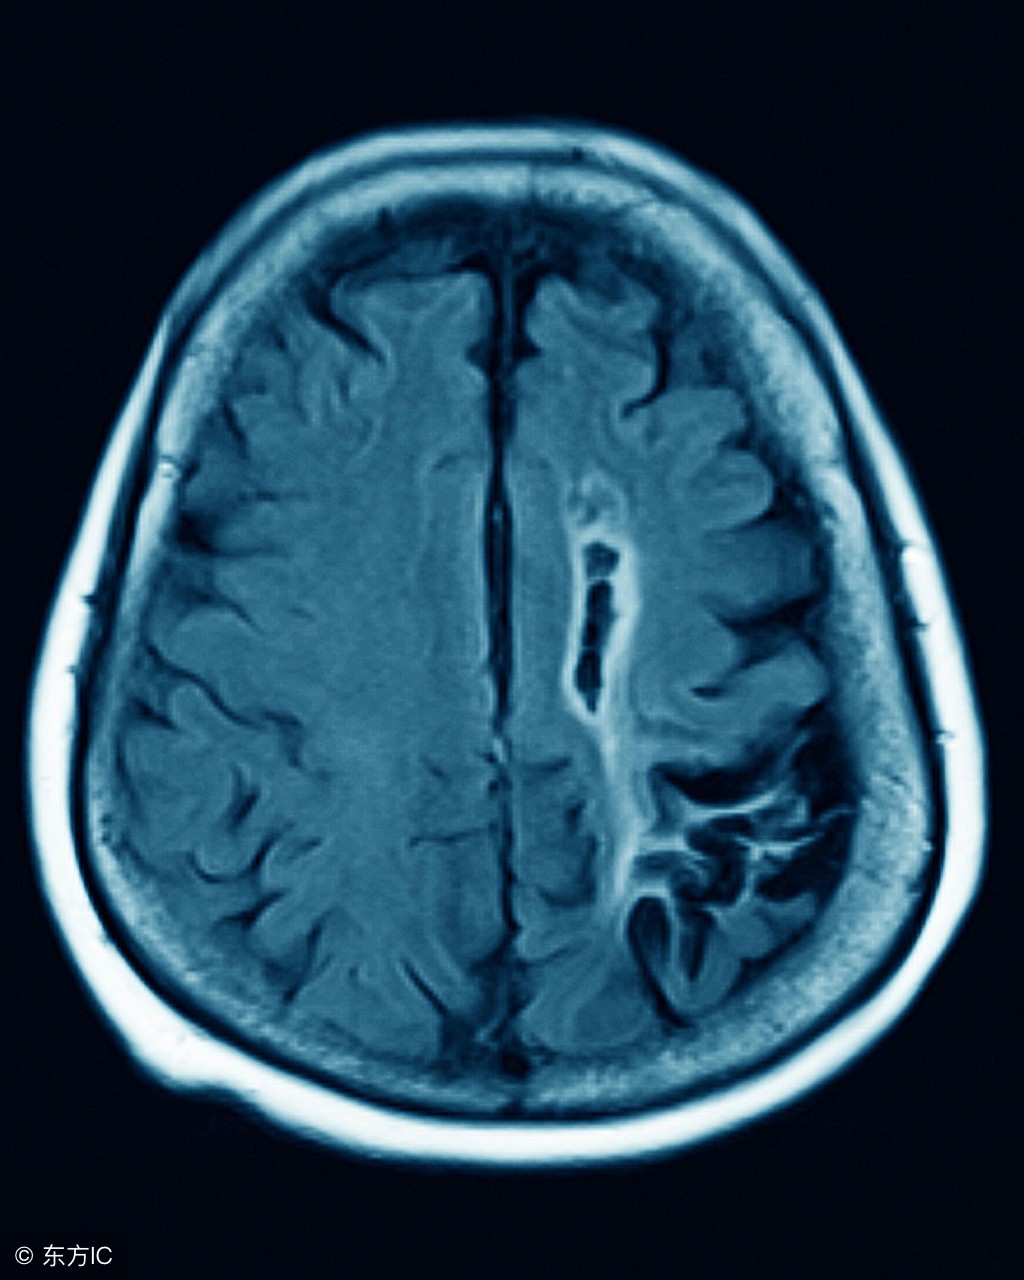

小脑萎缩就会导致患者在行为方面或者是语言上跟不上节奏,这会给患者的生活带来极大的影响,所以说我们建议哪些小脑萎缩的患者应该去医院及时的去接受正规治疗。小脑萎缩的这种疾病主要的发病人群是身体已经开始出现退化了的老年人的身上,它是会让老年人开始失去大脑当中的记忆,我们应该理解和帮助他们积极的去参与小脑萎缩的治疗。